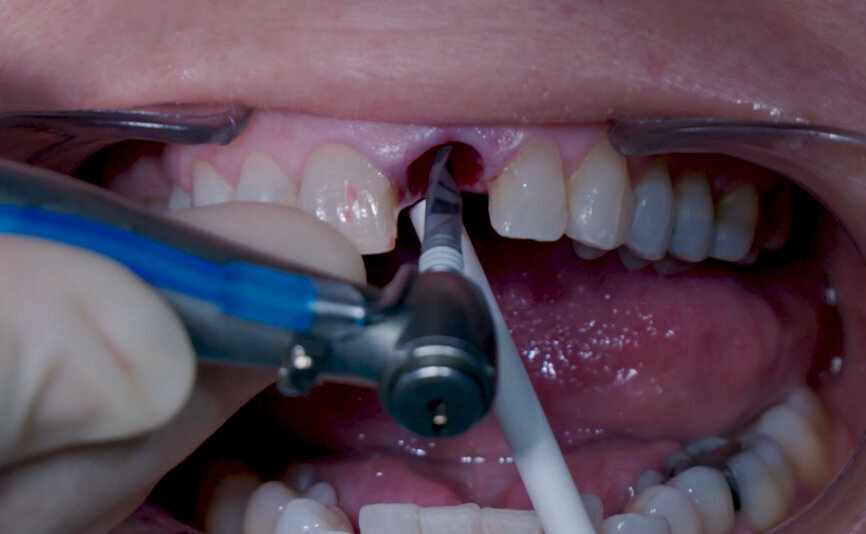

Fig. 5: Initial osteotomy with needle drill.

Fig. 6: Osteotomy with Ø 2.2 mm

drill.

Intra-sulcular incisions were performed to release the marginal gingival fibres to allow a minimally invasive extraction. The socket was carefully cleaned to remove any ligament and debris left. Special attention was given to assessing the alveolar wall integrity. A distance of 3 mm was observed between the gingival margin and the labial wall margin. Implant bed preparation considered a medium-density bone workflow, starting with the needle drill aimed at the palatal wall to create an entry point for the next drills, creating an osteotomy that allows for a greater area of implant engagement (Fig. 5). The Ø 2.2 mm pilot drill was used to the respective implant length planned, followed by the use of an alignment pin to check the 3D orientation (Figs. 6 & 7). The Ø 2.8 mm and Ø 3.2 mm drills were used to finalise the osteotomy (Fig. 8). The site was then properly probed to assess for possible wall perforation. A 4 × 14 mm implant was placed, starting with the surgical handle engaging the apical part of the implant, following the same orientation as that of the needle drill and correcting the implant direction as it moved within the osteotomy (Figs. 9 & 10). Primary stability (45 Ncm) was achieved at the final position. After placement, the implant position was verified horizontally with an occlusal mirror and vertically with a surgical probe, and at this point, the abutment gingival height was selected (Figs. 11 & 12). A healing abutment was placed on to the implant (Fig. 13) to protect the connection so that granular bone substitute (Straumann XenoFlex) could be applied in the gap between the implant and labial wall. This was gently compacted in with the 2.8 mm side of the surgical probe (Figs. 14–16). Collacone (botiss biomaterials) was used to keep the bone granules away from the gingival margins in order to avoid softtissue fenestration and fibroblastic infiltration (Figs. 17 & 18).